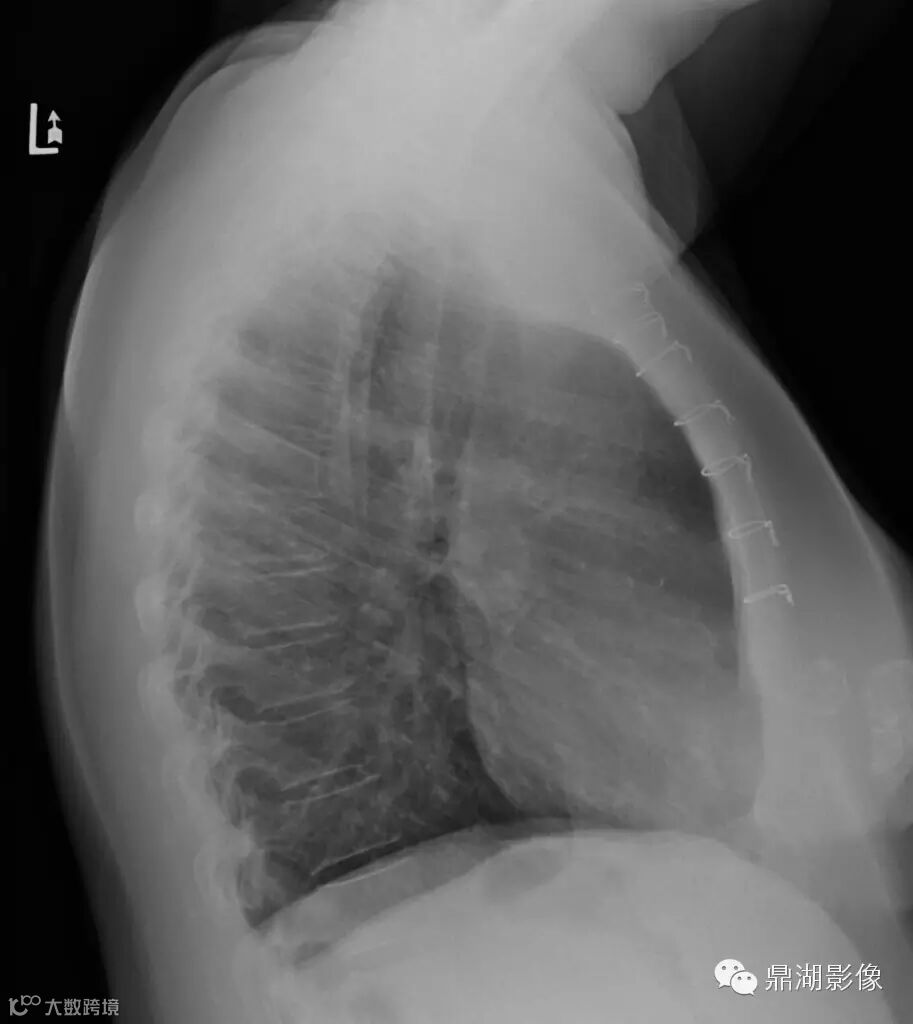

女,60,双侧乳房成形术数年,发现无痛性肿块数月。

双侧乳腺可见环状钙化

临床诊断:乳腺脂肪坏死

脂肪坏死临床及X线表现有如下特点:① 多有外伤、医源性损伤的病史,少数由导管扩张、炎症引起;② 临床上多为无痛性肿块和结节,质地偏硬,边缘欠清晰,少数有压痛;③伴有淋巴结肿大者,多为反应性增生,淋巴结光滑、质软、活动、无融合;④ 随访观察肿块无增大,反而逐渐缩小;⑤X线上脂性囊肿伴蛋壳样钙化以及皮下脂肪层内斑片状、星芒状、索条状及网状影为脂肪坏死的特征性表现。